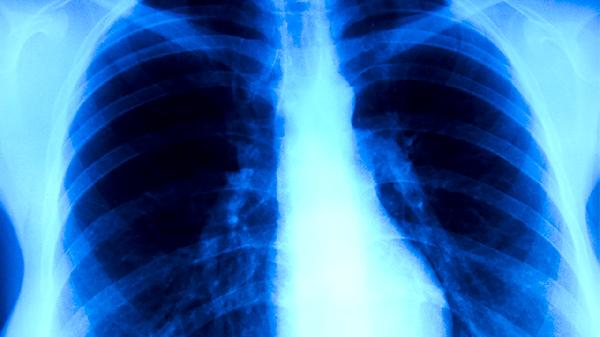

肺结核患者治疗期间需定期复查胸部影像学和痰菌检查,评估治疗效果。同时应注意加强营养支持,保证优质蛋白和维生素摄入,避免劳累和密切接触他人。出现药物不良反应如皮疹、视力模糊等症状时,应及时就医调整用药。完成全程规范治疗是治愈肺结核的关键,患者应严格遵医嘱服药,不可自行增减药量或中断治疗。